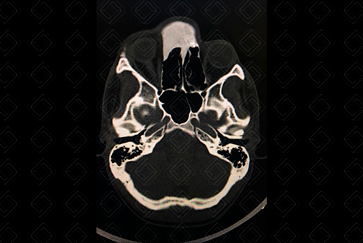

Texto alternativo para a imagem Figuras 1 e 2. Créditos: Dra. Elazir Mota - Rio de Janeiro/RJ

Descrição das figuras 1 e 2: Tomografia computadorizada de crânio evidenciando lesão expansiva, predominantemente hiperdensa, com aspecto em vidro fosco, na região frontal direita estendendo-se às células etmoidais e cavidade nasal bilateralmente (seta vermelha).

• Tomografia computadorizada: Característica da lesão, vemos que ela apresenta a clássica apresentação em “vidro fosco” ou “vidro despolido”. Esse aspecto de imagem deve nos fazer pensar na possibilidade de displasia fibrosa e sugerir seu diagnóstico (figuras acima);